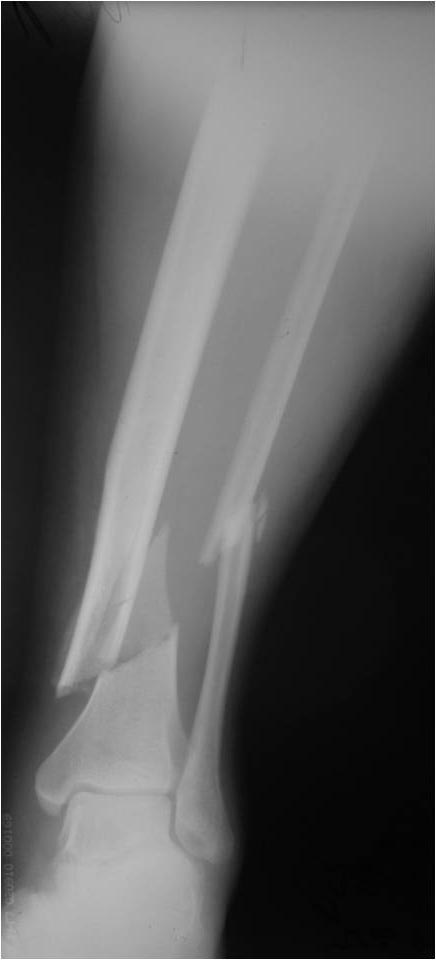

Re: Деформация фиксатора после падения

первичные снимки b послеоперационные качеством получше.